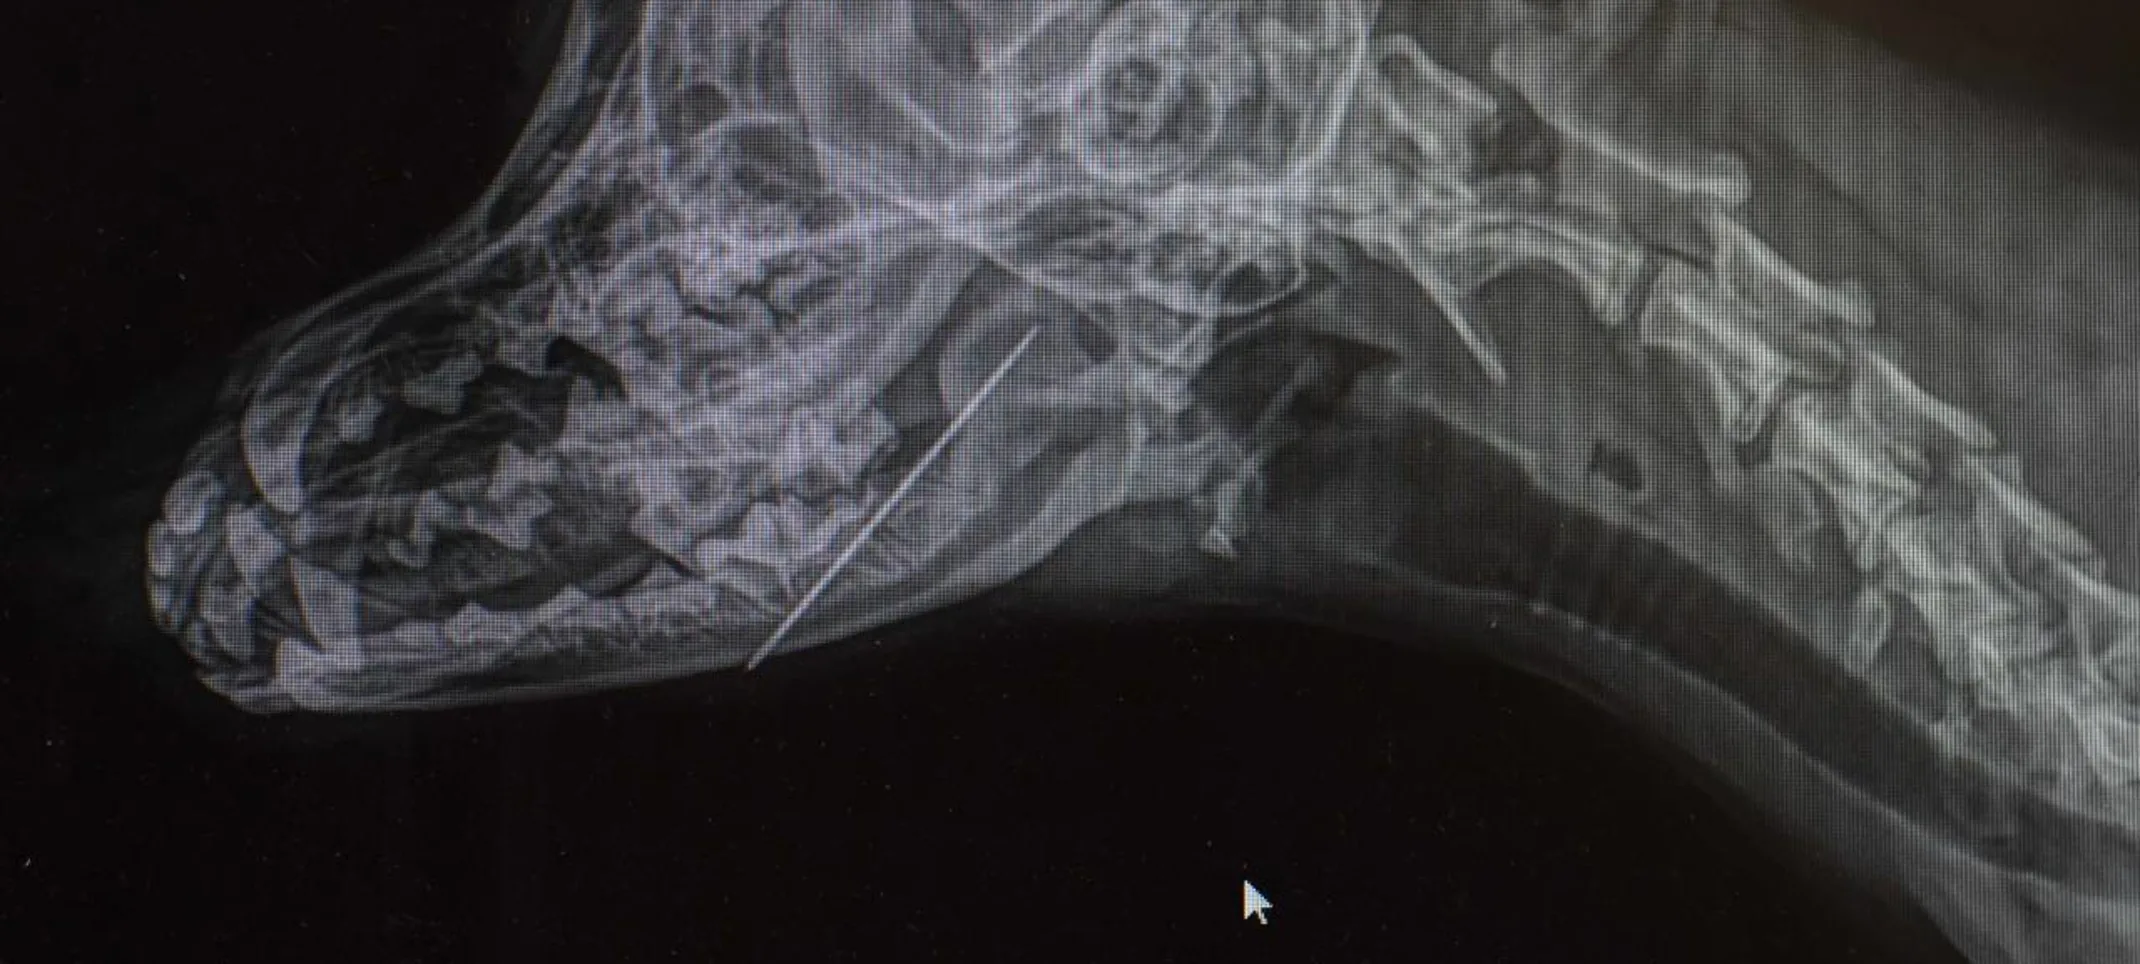

Radiography, also known as X-rays, is one of the most common and valuable medical diagnostic tools. X-rays are highly useful for screening areas of the body that have contrasting tissue densities, or when evaluating solid tissues.

X-rays can be used to detect a variety of ailments in animals including arthritis, tumors, bladder and kidney stones, and lung abnormalities such as pneumonia. They are also used to evaluate bone damage, the gastrointestinal tract, respiratory tract, genitourinary system, organ integrity, and even identify foreign objects that may have been ingested. Dental radiographs help distinguish healthy teeth from those that may need to be extracted and identify any abnormalities beneath the gums including root damage, tumors, and abscesses. In some cases, we may need to sedate your pet or use short-acting general anesthesia.